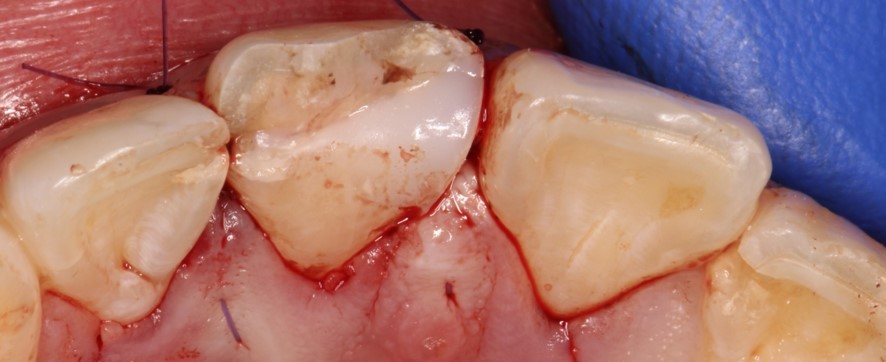

Спустя 2 недели

Воспроизвел временную реставрацию на момент эндодонтического лечения

Спустя 2 недели после операции